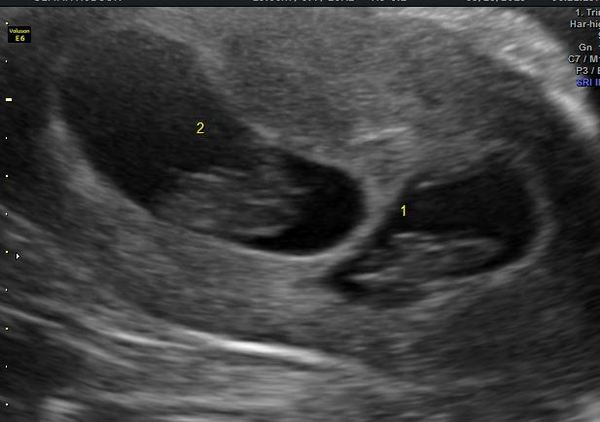

KittenMittens1 · 17/10/2019 09:12

Here are my twinnies, due May 4th. (Star Wars Day)

i'm 11+3 today. got my 12 week scan on my birthday next week Smile